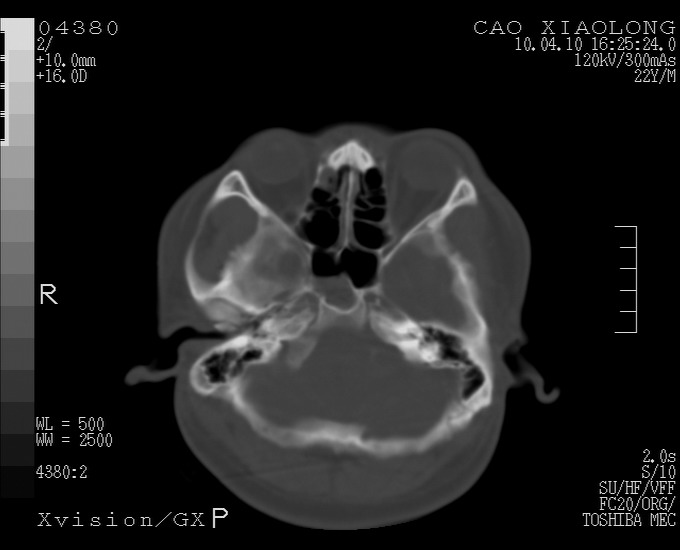

以下是引用随光逐影在2010-4-11 11:00:00的发言:[br]1)左侧额颞顶部硬膜下血肿。2)蛛网膜下腔出血。3)右侧颞顶部颅骨线形骨折。[br][br]20小时后复查:左侧额颞叶脑挫裂伤;左侧额颞顶部硬膜下血肿及蛛网膜下腔出血有吸收表现;右侧颞顶部颅骨线形骨折。[br]